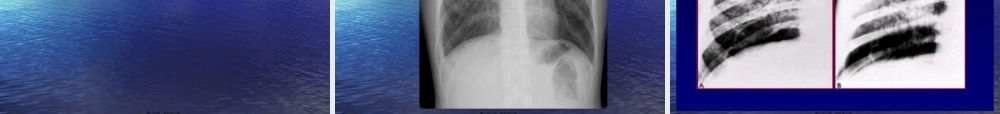

肺结核肺结核(TB)(TB)的影像的影像(yǐnɡxiànɡ)(yǐnɡxiànɡ)诊断诊断(pulmonarytuberculosis(pulmonarytuberculosis))第一页,共五十二页。•学习目的:掌握各型肺结核的X线表现,熟悉其病理改变及分型,了解(liǎojiě)其临床表现。•学习要求:通过本次课学习,能阅读肺结核平片并能作出诊断。•学习重点及难点:继发型肺结核的典型X线表现及鉴别诊断。第二页,共五十二页。•病例讨论:患者,男,26岁,近2月咳嗽、咯血、低热、盗汗、乏力。1、初步(chūbù)诊断为?2、我们应该建议病人作哪些辅查?第三页,共五十二页。肺结核(TB)的影像(yǐnɡxiànɡ)诊断(pulmonarytuberculosis)•概论:•肺结核是由结核杆菌在肺内所引起的一种常见的慢性疾病。•肺结核的诊断主要(zhǔyào)以临床症状、痰检、X线检查及CT检查等为依据。其中X线检查及CT检查在发现病变、鉴别诊断及动态观察方面均具有重要作用。第四页,共五十二页。一、临床(línchuánɡ)与病理•(一)肺TB的临床表现:•肺TB的临床表现与感染的结核杆菌数量、毒力及机体的免疫反应和变态反应状态(zhuàngtài)有关,也与病变的发展阶段有关。•有些病人可无任何临床症状,在体检时发现。•有些病人则以咳嗽、咯血及胸痛为主要表现,但有的病人除以上症状外,还有较明显的全身中毒症状,表现为低热、盗汗、乏力、食欲减退、明显消瘦等。第五页,共五十二页。•(二)肺TB的病理演变过程•吸收渗出增殖淋巴(línbā)播散•纤维化愈合干酪坏死恶化血行播散•钙化•空洞愈合液化空洞支气管播散第六页,共五十二页。•结核病的分类:•1、原发型肺结核(Ⅰ型):包括原发综合征和胸内淋巴结结核。•2、血行播散型肺结核(Ⅱ型):包括急性粟粒型肺结核和亚急性/慢性血行播散型肺结核。•3、继发型肺结核(Ⅲ型):包括渗出浸润为主型、干酪为主型和空洞为主型肺结核。•4、结核性胸膜炎(Ⅳ型):包括结核性干性胸膜炎、结核性渗出性胸膜炎、结核性脓胸。•5、其它(qítā)肺外结核(Ⅴ型):按部位及脏器命名,如骨结核、肾结核、肠结核及结核性脑炎等。第七页,共五十二页。•机体初次感染TB杆菌所引起,常见于儿童,成人也可见(由发生变异的菌株引起)。•(一)原发综合征:由肺部原发灶、局部淋巴管炎和所属淋巴结炎三者合称。•(二)胸内淋巴结TB:当原发灶完全吸收时,纵隔and/or肺门淋巴结肿大为其重要表现。分炎症(yánzhèng)型和结节型。一、原发型肺TB第八页,共五十...

1、当您付费下载文档后,您只拥有了使用权限,并不意味着购买了版权,文档只能用于自身使用,不得用于其他商业用途(如 [转卖]进行直接盈利或[编辑后售卖]进行间接盈利)。

2、本站所有内容均由合作方或网友上传,本站不对文档的完整性、权威性及其观点立场正确性做任何保证或承诺!文档内容仅供研究参考,付费前请自行鉴别。

3、如文档内容存在违规,或者侵犯商业秘密、侵犯著作权等,请点击“违规举报”。